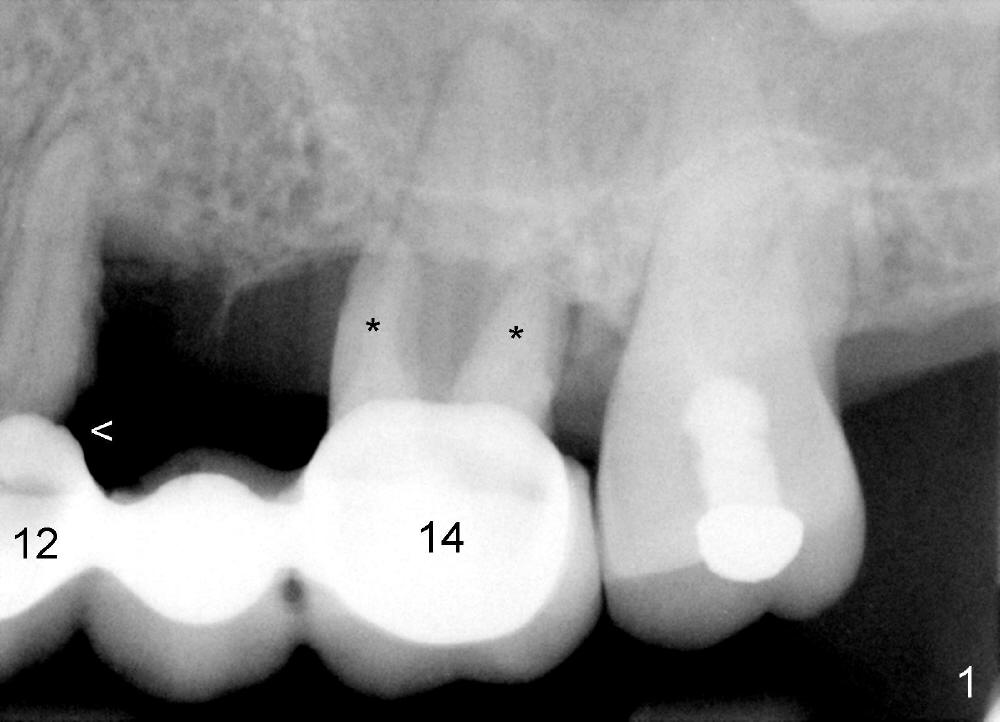

A 53-year-old lady has a failing bridge (Fig.1). There is severe bone loss around the buccal roots of #14 (*). Purulent discharge is from the gingival sulcus (Fig.2 <) with localized gingival erythema and edema (*). When the bridge is removed, the tooth #12 is found nonsalvageable (Fig.3,4). These two teeth are to be replaced by immediate implants (Fig.5). Although the sinus floor is low buccally (arrowheads), a 6x14 mm gingiva-level implant can be placed in the septum close to the palatal socket or in the palatal socket at the site of #14.